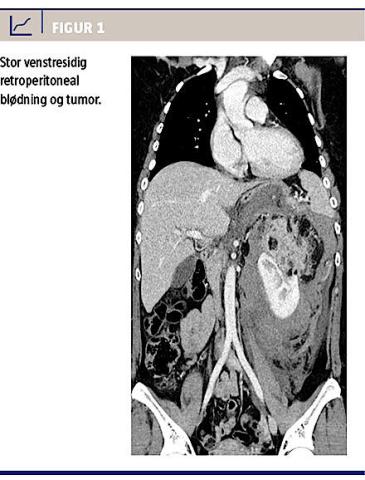

Da patienten havde faldende hæmoglobinniveau og vigende blodtryk, blev der aftalt akut overflytning til et døgnbemandet emboliseringsafsnit mhp. invasiv radiologi og embolisering. Under transporten måtte patienten transfunderes med fem SAG-M, fire portioner kolloid ekspander og to liter isotonisk NaCl. Ved ankomst blev der udført renal angiografi, hvorved der blev fundet to blødende arteriegrene. Disse blev lukket ved selektiv embolisering (Figur 2).